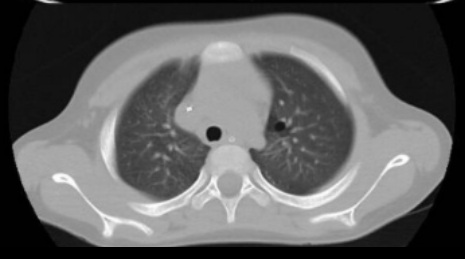

6. TC tórax

TC TÓRAX: En segmento apicoposterior del lóbulo superior de pulmón izquierdo, se observan

imagen quística de paredes finas.